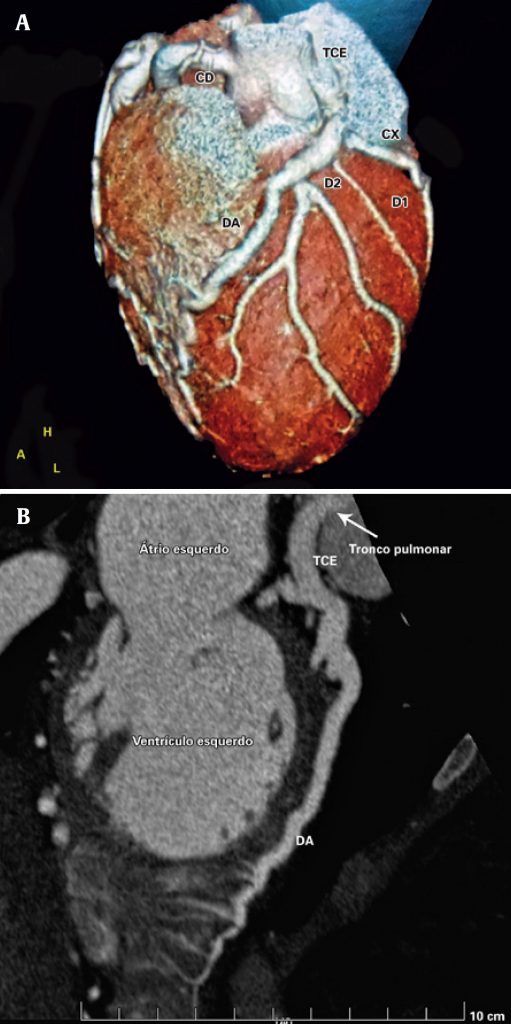

Figura 2

(A e B) Angiotomografia coronariana. Tronco da artéria coronária esquerda (TCE) origina-se no tronco pulmonar, medindo 7,3 mm de diâmetro. A artéria descendente anterior (DA) contorna o ápice do ventrículo esquerdo, medindo até 6,8 mm de diâmetro. A artéria circunflexa (Cx), de grande importância, apresenta ectasia em seu terço proximal, medindo até 6 mm de diâmetro. A artéria coronária direita (CD) origina-se do seio coronário direito, medindo até 8 mm no seu maior diâmetro.